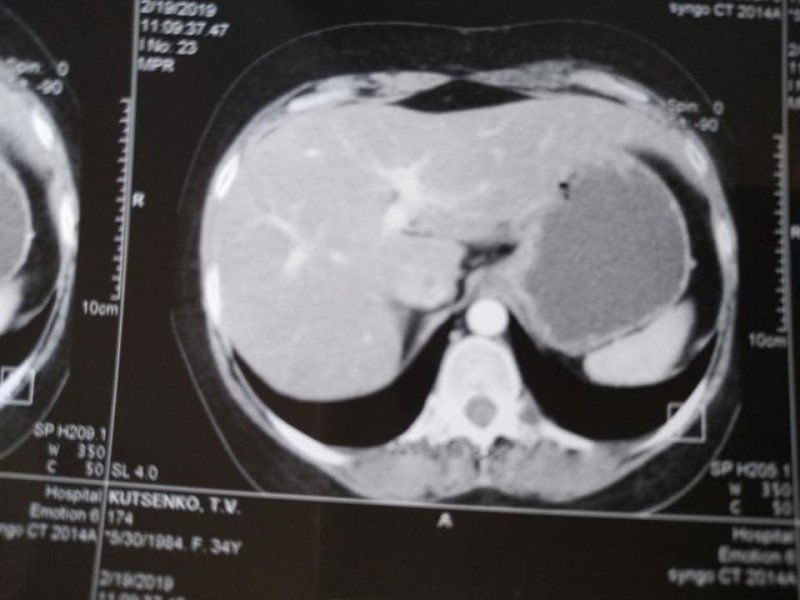

«У мене метастази, 4 стадія, але постійна від початку лікування позитивна динаміка. З 5 пухлин різних за розмірами в печінці, залишилася одна 12 на 10 мм, яка була на початку 50 мм. На першому фото печінки видно плями темні -це вони, метастази, а на другому фото теперішній стан. Це дуже успішне лікування. Ще трішки і я надіюсь і ця пухлина теж зникне», – розповіла вона.Фото печінки до лікуванняФото печінки після лікування